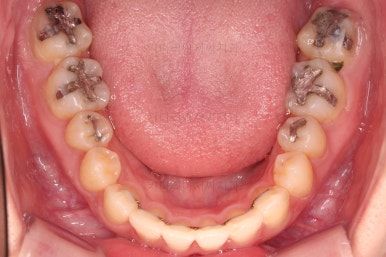

4. 마무리

치료 종료 시 입안의 모습입니다.

윗니만 발치를 했지만 교합이 잘 맞고요.

한 쪽 송곳니가 없지만 기능적으로 전혀 문제를 못느끼실 교합을 맞춰놨고요.

위아랫니 가지런해졌고요.

대신 중앙선은 약간 틀어져 있는데요.

한 쪽은 송곳니가 없고 한 쪽은 작은 어금니를 발치했기 때문인데요.

18개월이라는 짧은 기간동안 부정교합, 덧니, 심지어 매복치아까지 개선했는데 양측 치아 사이즈 문제로 생기는 중앙선 정도는 아무 문제가 안되는거죠.